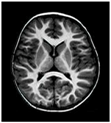

This process covers the image pixels and resolves the uncertainty issues while segmenting the affected region. The effective computation of pixel information helps preserve the edge information, reducing the complexity involved in the inner details processing. According to the discussion, the segmented regions are illustrated in Table 2.

Table 2.

Sample brain tumor region segmented images.

The segmented region and respective edge-related area are illustrated in Table 2. The segmented regions are processed by feature extraction to derive the various information from MRI images. The effective utilization of seed points helps to identify the candidate region successfully, improving the overall tumor recognition accuracy.